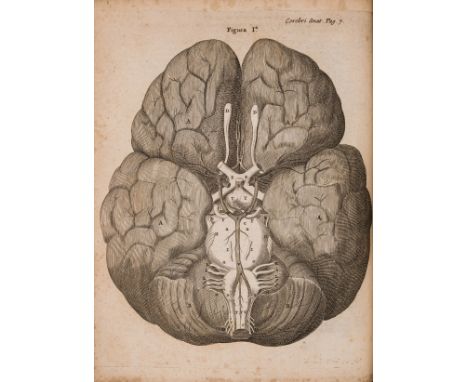

Willis (Thomas) Opera Omnia, engraved additional pictorial title and 37 plates, some folding, lacking portrait, some spotting, engraved title lacking upper outer corner just touching border (repaired), one or two plates torn and repaired, modern morocco-backed marbled boards, Amsterdam, H.Wetsten, 1682 § Motherby (George) A New Medical Dictionary, third edition, 30 engraved plates at end (misbound), a little light spotting or staining, modern morocco-backed cloth, [Wellcome IV.188], J.Johnson, 1791 § Freind (John) Opera omnia medica, first collected edition, initial imprimatur leaf, half-title, engraved portrait and title-vignette, title lightly soiled and with stain to lower outer margin, modern calf-backed marbled boards, spine gilt, [Wellcome III.66], John Wright, 1733, all ex-library copies with traces of stamps to tiles and some plates; and another, 4to & folio (4) ⁂ The first is the third and best edition of the collected works of Willis, a founding member of the Royal Society and a pioneer in research into the anatomy of the brain, nervous system and muscles. The work includes his Cerebri anatome in which he coined the term "neurology". He also discovered the "Circle of Willis", a circle of arteries on the base of the brain.